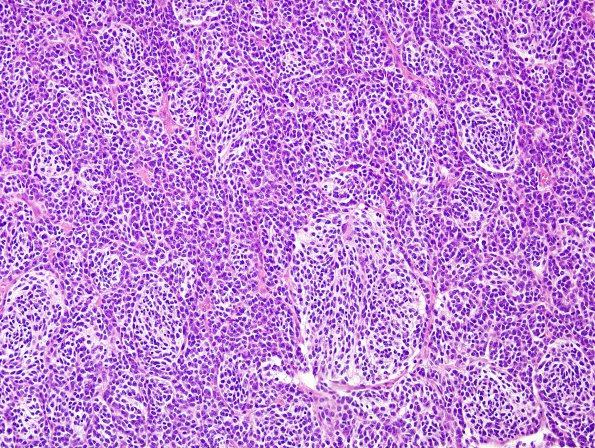

Washington University Experience | NEOPLASMS (EMBRYONAL) | Medulloblastoma, Histologically Defined | Extensive Nodularity (MBEN) | 8B2 Medulloblastoma, desmoplastic (Case 8) H&E 10

Among the sheets of monomorphic cells are islands of tumor cells with increased cytoplasm compared to the surrounding tumor and a lesser degree of mitotic activity. Within the pale islands are cells with a neurocytic look and occasional ganglion-like cells. (H&E)